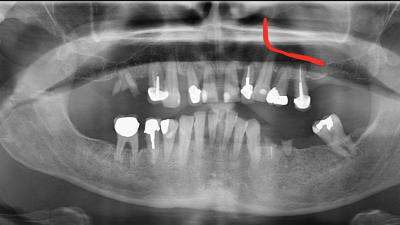

Implants Implantology Innovations A Transnasal Implant Technique By Cesar Augusto Montanari Dalmolin, DDS, Daniel Baptista, DDS, Eduardo Meurer, DDS, Fabio Andretti, DDS, João Ricardo Almeida Grossi, DDS, Vanderlim Branco Camargo, DDS June 01, 2023 7 min read